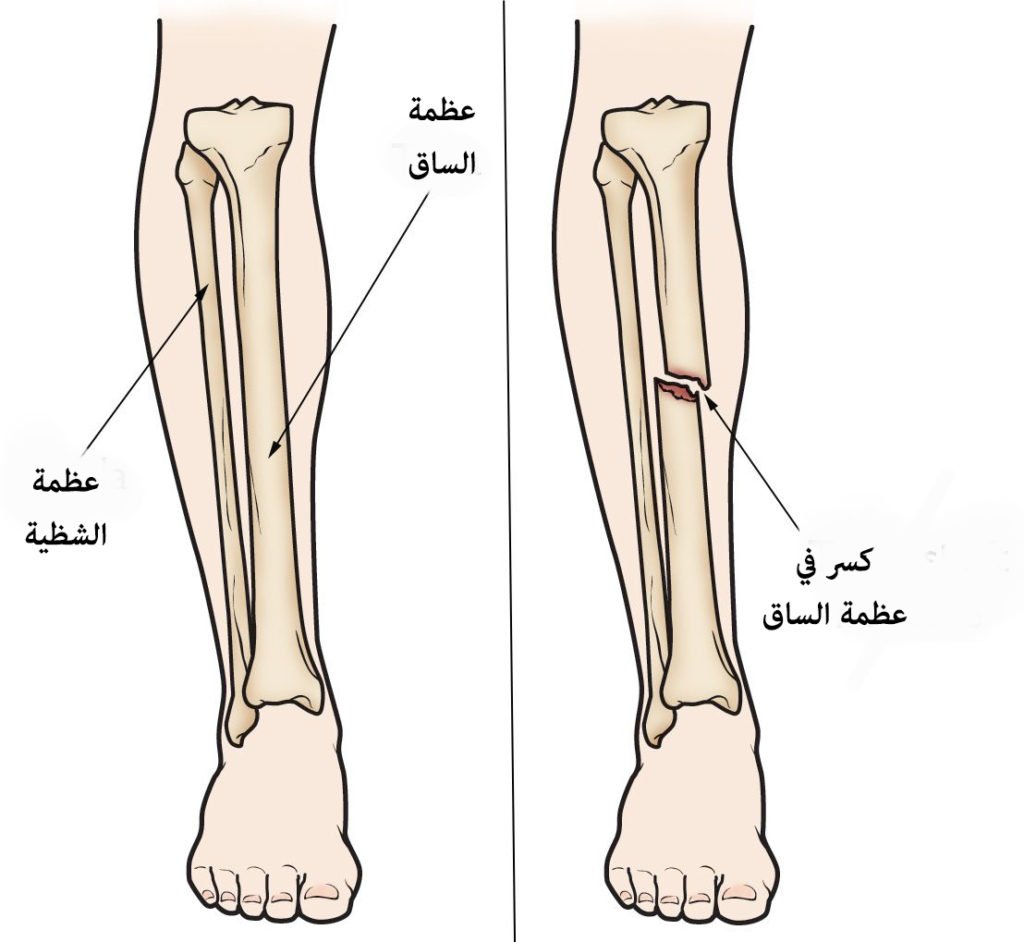

Перелом большой берцовой кости - серьезное повреждение, сопровождающееся болезненными ощущениями и нарушением функции ноги. На этой странице вы найдете много фотографий, позволяющих вам более детально изучить эту травму.

Здесь представлены медицинские изображения переломов большой берцовой кости, сделанные врачами в процессе диагностики и лечения. Вы сможете увидеть, как выглядит этот тип травмы на рентгеновских снимках и других медицинских изображениях.